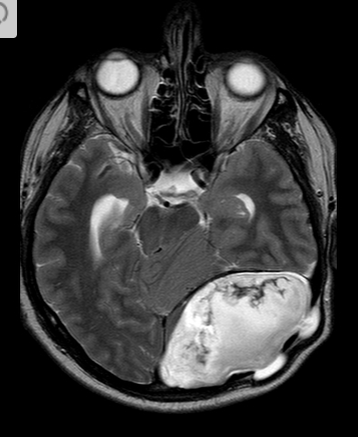

39 anos

Meduloblastoma Massa cerebelar na linha média que protrui pra dentro do quarto ventrículo.